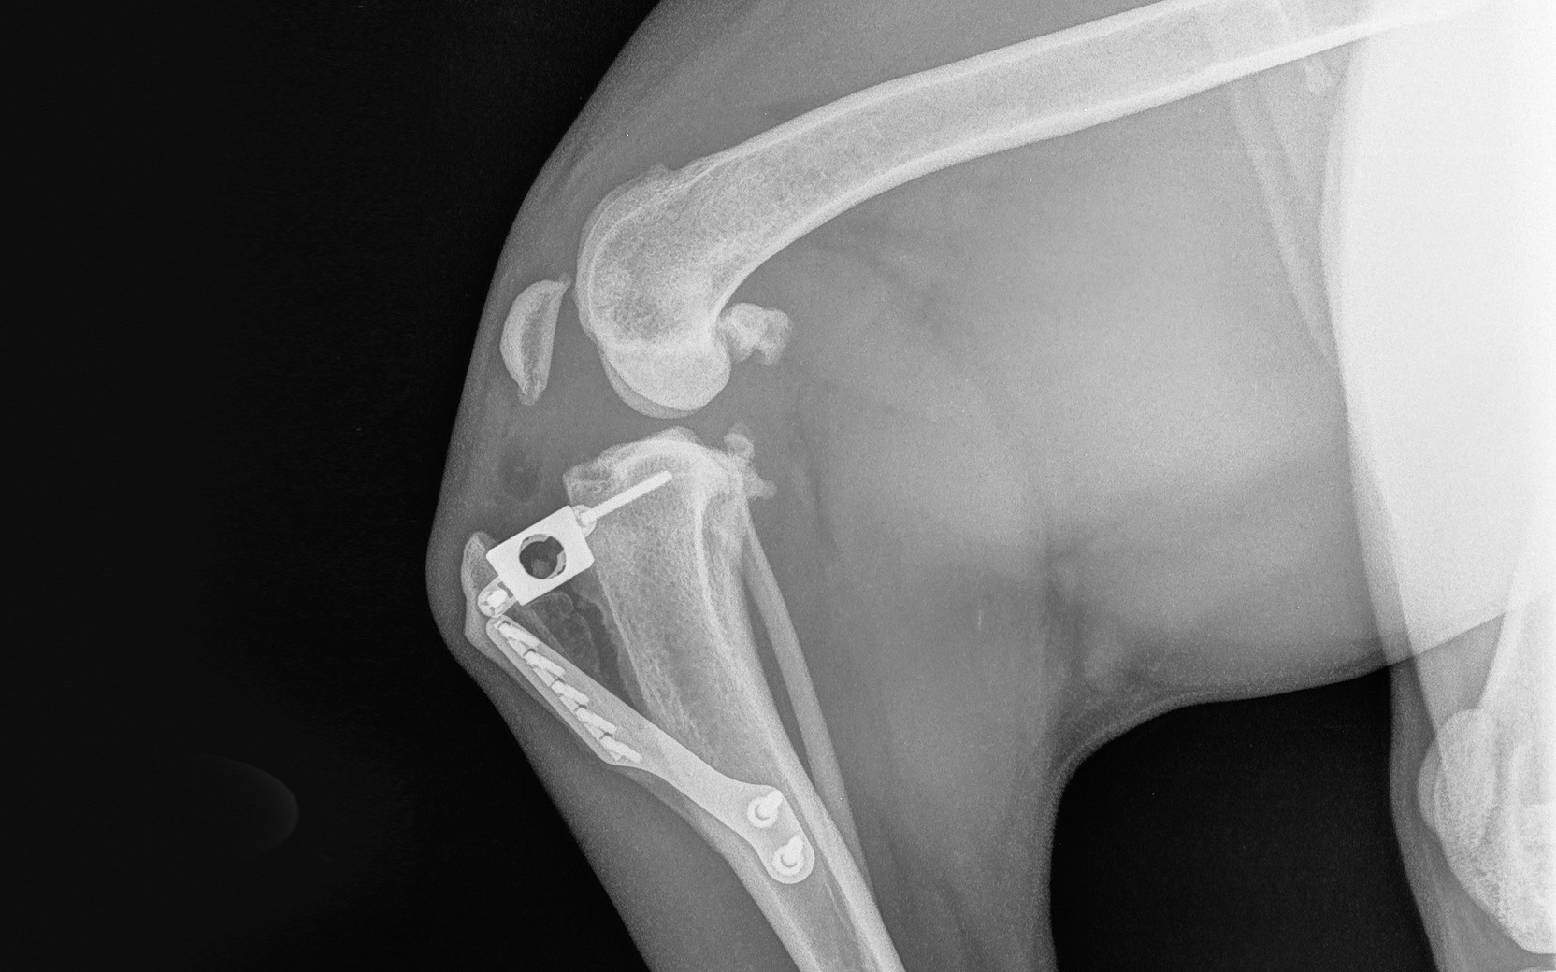

Die Tibial Plateau Leveling Osteotomy (TPLO) ist ein Operationsverfahren, bei dem mit einem runden Schnitt der Unterschenkelknochen durchtrennt und mit speziell dafür vorgesehenen Platten in einem veränderten Winkel wieder verschraubt wird. Die Geometrie des Knies wird damit insoweit verändert, als dass die Zugkräfte, die auf das vordere Kreuzband wirken, aufgehoben werden.

Durch die Tibial Tuberosity Advancement (TTA) wird ebenfalls die Biomechanik des Kniegelenks durch einen Knochenschnitt verändert, jedoch mit einer weitaus weniger invasiven Operationsmethode als bei der TPLO. Hierbei wird der vordere, nicht Gewicht tragende Rand des Unterschenkelknochens durchtrennt, nach vorne verlagert und mit Hilfe spezieller Platten und Schrauben in dieser Position fixiert. Der Ansatzpunkt des Kniescheibenbandes wird dadurch so weit nach vorne verschoben, dass es im rechten Winkel zur Gelenkoberfläche des Schienbeins liegt und damit die Überbeweglichkeit im Kniegelenk einschränkt. Die Dauer dieser Operation ist wesentlich kürzer als bei einer TPLO und eine Eröffnung des Kniegelenks ist während der OP nicht notwendig. Dies führt zu einem deutlich niedrigeren Narkose- und Infektionsrisiko. Häufig ist der Erfolg dieser Methode bereits ein paar Tage nach der Operation durch die Belastung des Beines zu erkennen.

Der Heilungserfolg sollte ungefähr zwei Monate nach der Operation durch erneute Röntgenaufnahmen kontrolliert werden. Um den Muskelaufbau zu unterstützen, können begleitend physiotherapeutische Maßnahmen eingesetzt werden.